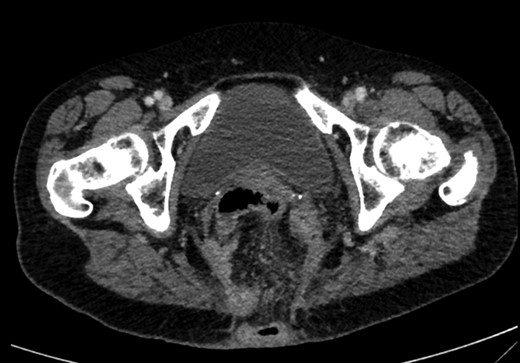

On examination, she was febrile. Her abdomen was generally tender. Bowel sounds were present and up to that time her stoma was working. Her perineal hernia was red and tender. Her initial CXR (Fig. 1) did reveal a sliver of gas underneath her right hemidiaphragm and in keeping with her abdominal findings she progressed to further imaging. CT abdomen pelvis with contrast showed pneumoperitoneum (Fig. 2) with ‘a tiny pocket of air is also seen adjacent to a loop of bowel in the pelvis posterior to the bladder’. ‘Exact site of perforation has not been demonstrated but could possibly be in the bowel loops in the perineum’ (Figs 3 and 4).

Sagittal view showing small bowel loops in pelvis with perineal hernia.